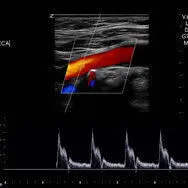

The carotid artery ultrasound scan is most frequently performed to detect narrowing, or stenosis of the carotid artery, a condition that substantially increases the risk of stroke. It is used as a general screening tool for patients over 45 years or if you have history of cardiovascular disease or at risk of stroke.

The scan will evaluate the size, shape, and outline, measuring also the blood flow velocities in the:

Common pathology which can appear on the scan are plaque deposits and subsequent narrowing of the arteries particularly the internal carotid artery which supplies blood to the brain.